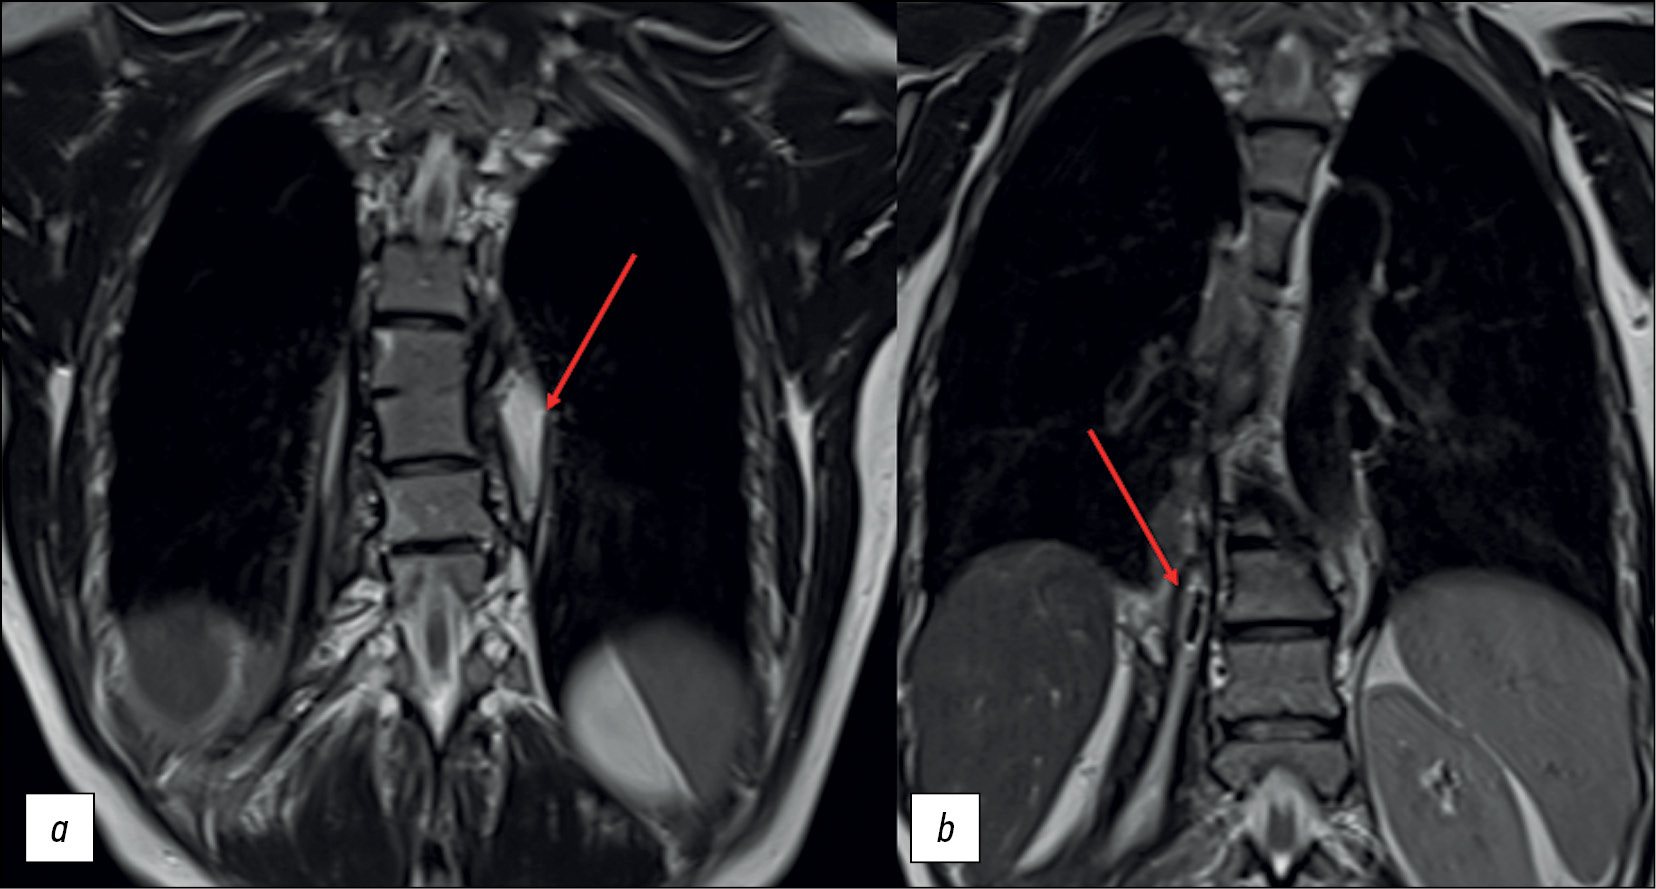

A follow-up thoracic and lumbar spine MRI performed in the hospital revealed stable changes in the ТhVII–ТhVIII vertebral bodies and bilateral paravertebral abscesses (Figure 4).

Fig. 4. Thoracic and lumbar spine MRI: T2WI mode, coronal plane. Bony and fibrous ankylosis ТhVII–ТhVIII and paravertebral abscesses (arrows) on the left (а), with air bubbles on the right (b).